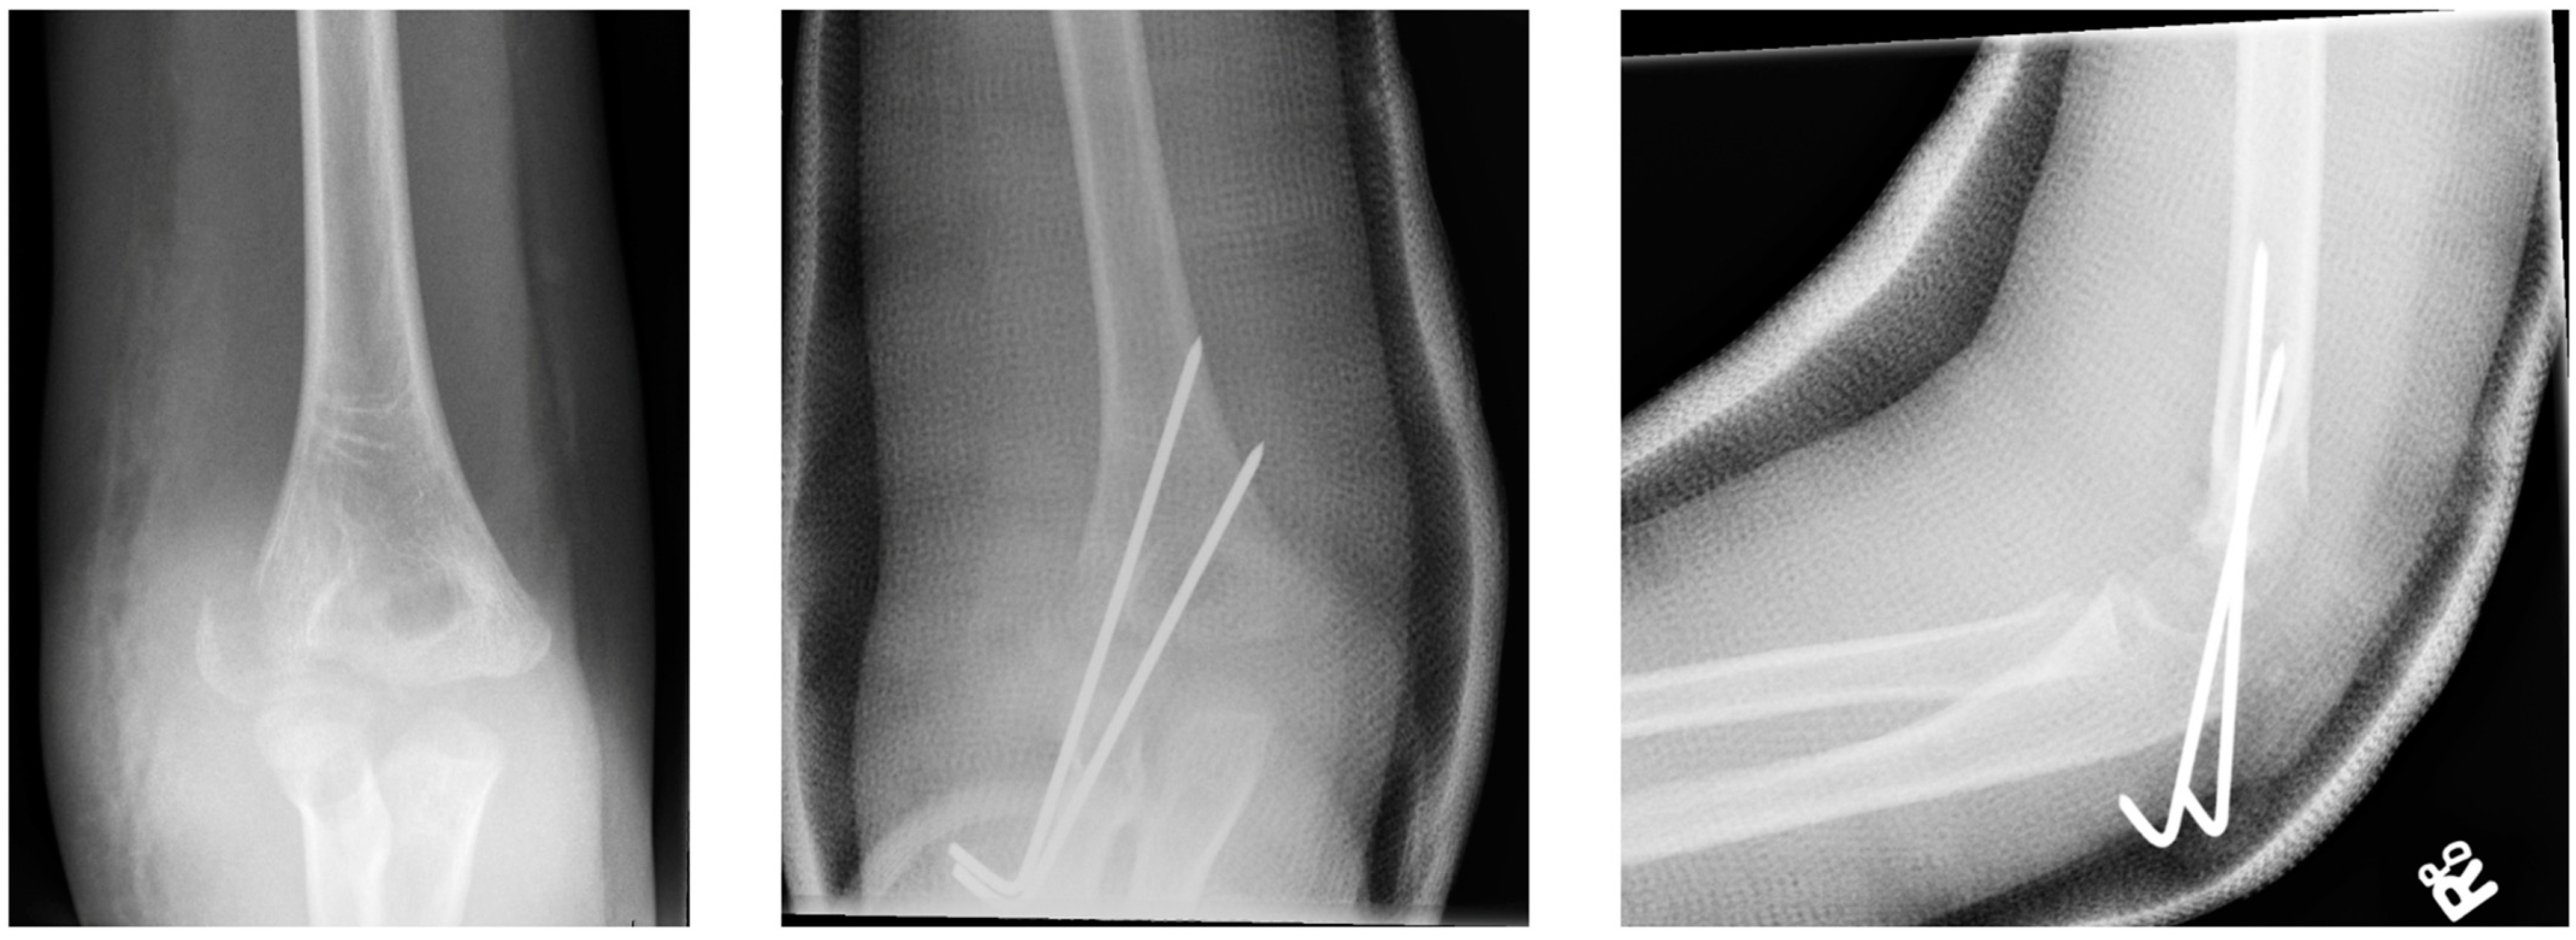

3.2.1. Closed Reduction and Internal Fixation

3.2.2. Open Reduction and Internal Fixation